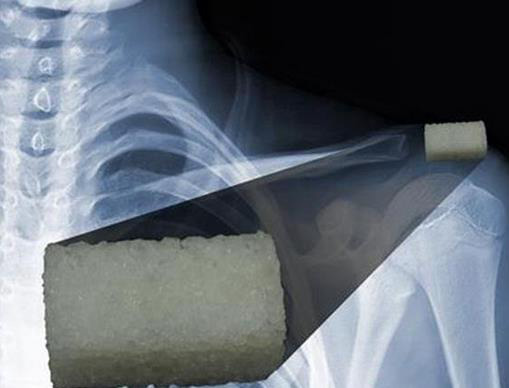

這使得它成為了用于制造植入物和骨組織的小部分替代物很有吸引力的材料?!拔覀兪褂玫氖橇u基磷灰石納米顆粒和可與人體兼容的聚合物,后者會在體液環(huán)境中降解。不過它會在足夠長的時間里提供結(jié)構(gòu)支撐,以便于天然骨骼的生長。”BUAP的研究人員補充說。具體來說,一種羥基磷灰石粉末被用作了骨填料。

最重要的是,這種新型的生物材料可以在孔隙率水平受控的條件下進(jìn)行3D打印,這使得它能夠適用于一系列廣泛的特定應(yīng)用。通過一種特殊的算法,醫(yī)生們可以設(shè)計三維結(jié)構(gòu)和圖案為每一名病人提供足夠的支持,然后將其3D打印出來。目前科學(xué)家們已經(jīng)為該數(shù)學(xué)模型提交了專利申請。這些研究人員已經(jīng)開始致力于在不久的將來3D打印骨骼。

而現(xiàn)在,他們正字尋求打印出1立方厘米的植入物。除此之外,該校醫(yī)學(xué)系也正準(zhǔn)備驗證這一材料的生物相容性。